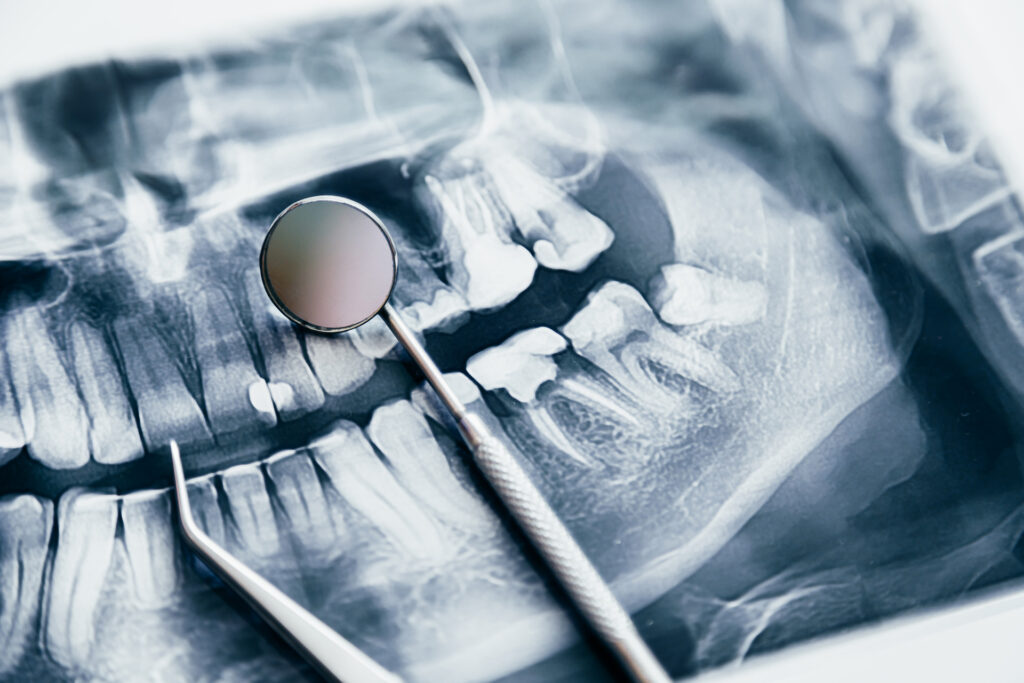

Dentists diagnose wisdom tooth decay through a combination of clinical examination and imaging. Distinguishing decay from normal eruption discomfort is especially important, since teething-related soreness can mimic the early signs of infection.

Visual inspections will reveal early signs, such as enamel breakdown, swelling or gum tenderness. Bitewing X-rays and panoramic scans will help detect cavities hidden below the gum line or inside impacted teeth, which are not visible to the naked eye. When the decay is complex or the impaction is severe, referral to an oral and maxillofacial specialist may be recommended for further evaluation.